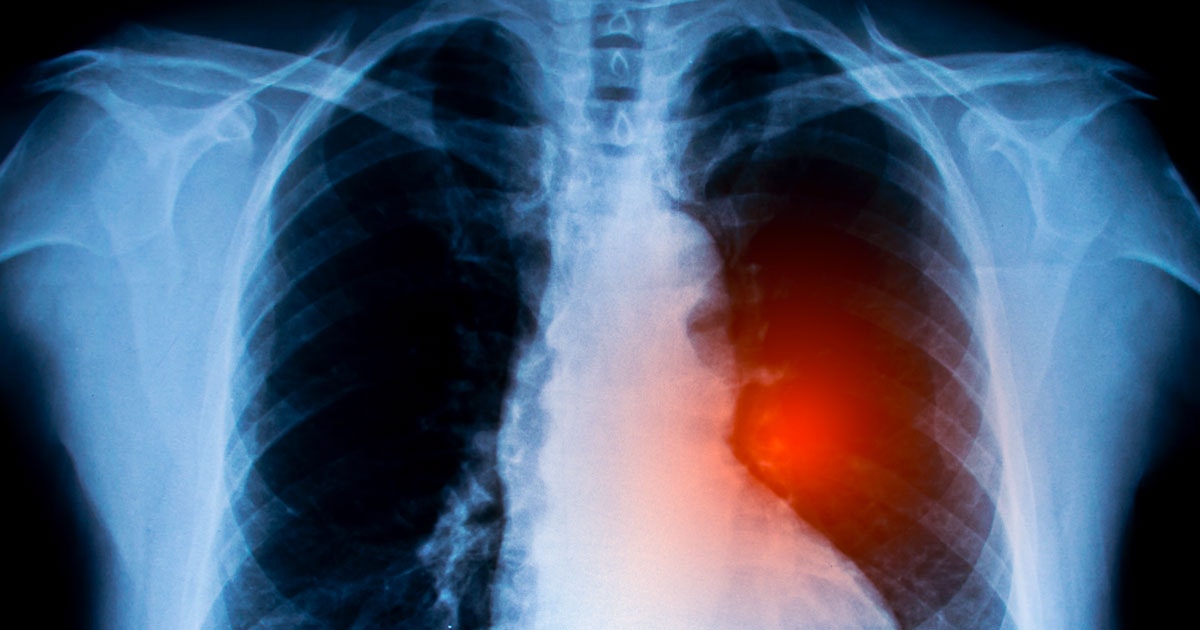

Esaminando i geni che si trovano comunemente nelle cellule tumorali, gli oncogeni, gli scienziati hanno scoperto che un particolare gruppo, gli oncogeni MYC, era sovrarappresentato dopo la chemioterapia ed era associato allo sviluppo della resistenza.

Fimepinostat, che è già in fase di sperimentazione clinica per il trattamento dei tumori cerebrali nei bambini, ha le giuste proprietà e successivi test sui topi hanno dimostrato che il farmaco ha ridotto le dimensioni dei tumori e aumentato significativamente la durata della vita degli animali da laboratorio.